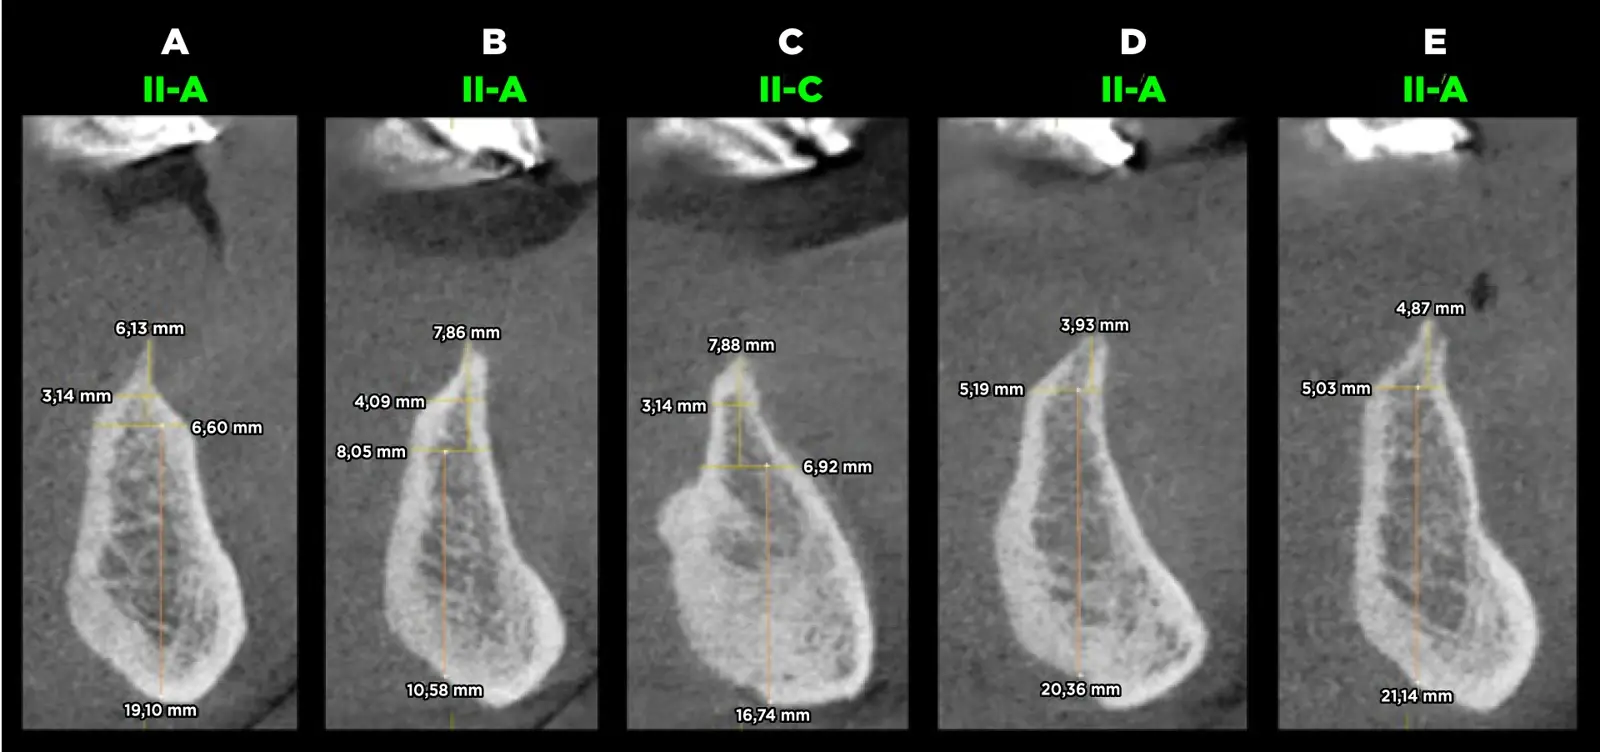

Se procedió con la confección de la placa base y los rodetes de cera previa estabilización oclusal mediante un encerado de diagnóstico y planificación. Se confeccionó la guía quirúrgica bien adaptada y en oclusión para corroborar la ubicación tridimensional de los implantes. El paciente acudió a la consulta con una tomografía computarizada volumétrica previa a la confección de la prótesis inferior, en donde se realizaron los cortes tomográficos teniendo en cuenta los reparos anatómicos. Se evaluó la calidad ósea y se planificó la colocación de cinco implantes en posiciones A, B, C, D y E, con la eliminación previa de estructura ósea debido al escaso ancho que ésta presentó y que dificultaría la preparación e instalación de los implantes (Figura 3).

Evaluación de la calidad ósea

Figura 3. Evaluación de la calidad ósea del paciente según la clasificación de Lenkholm y Zarb modificada por Rosas y cols. donde se observa el hueso tipo II-A y II-C en el paciente.